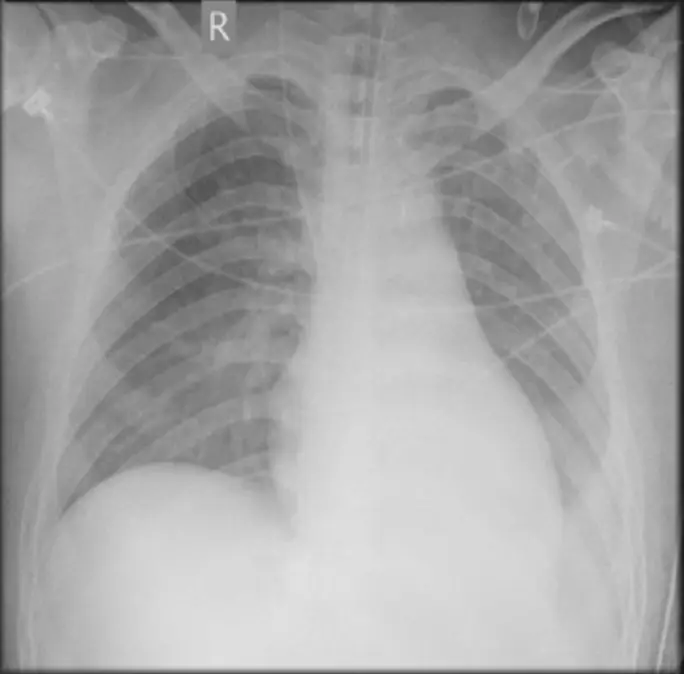

吳先生現年20歲,一向健壯,從事建築粗工,於3月22日有感冒流鼻水、發燒及咳嗽症狀,三天後更有全身倦怠及暈厥,乃至心疼,因心電圖及胸X光異常(如圖),而從急診住院。理學檢查:Consciousness: drowsy, E3VTM4;T:37.5 P:93 R:16及BP:82/65 mmHg; 頸靜脈怒張; 胸部有濕濁呼吸音; 心臟未有擴大,心音略為微弱,尚無S3或S4及心臟雜音可聞; 腹部未有腹水或肝脾腫大; 雙腳未見水腫。實驗室檢查:WBC,8.37 K/uL;RBC,4.35 M/uL;Plt,128 K/uL; Hb, 13.0 gm/dL;CK,514 U/L;CK-MB,43 U/L; Troponin I, 2.6 ug/L; CRP, 5.6 mg/dL。 本病人隨即進行下列臨床決策: (1) Continuous IV infusion of Dopamine at the dose of 7.8 mcg/kg/min,以穩定血壓及心跳及血氧 (2) 使用IV Heparin at the dose of 1000 u/hour,以預防血栓的形成 (3) 3月27日因持續性Ventricular tachycardia,採用Electric cardioversion不盡有效,而置放V-A ECMO及IABP (4) 3月28日進行Left ventricular assisted device,以維持左心室功能 (5) 3月29日Myocardial biopsy之病理確診後,使用IVIG,也使用Prednisolone、Cyclosporine及Azathioprine (6) 病情在3月31日後於焉穩定 從診斷及處置,本病例的處置尚稱成功。請問下列何者才是Evidence-based management?

**圖二:胸部X光(Ch